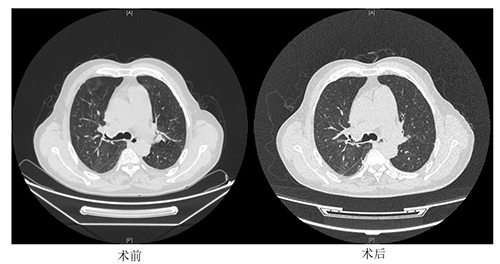

经球囊成形后,常先生肺动脉血流明显改善,并且肺静脉回流良好。动脉血流储备分数(FFR)由术前的0.16提升到0.64。压力导丝的指引使球扩效果良好,肺动脉功能已恢复,术后复查CT患者双肺无水肿。